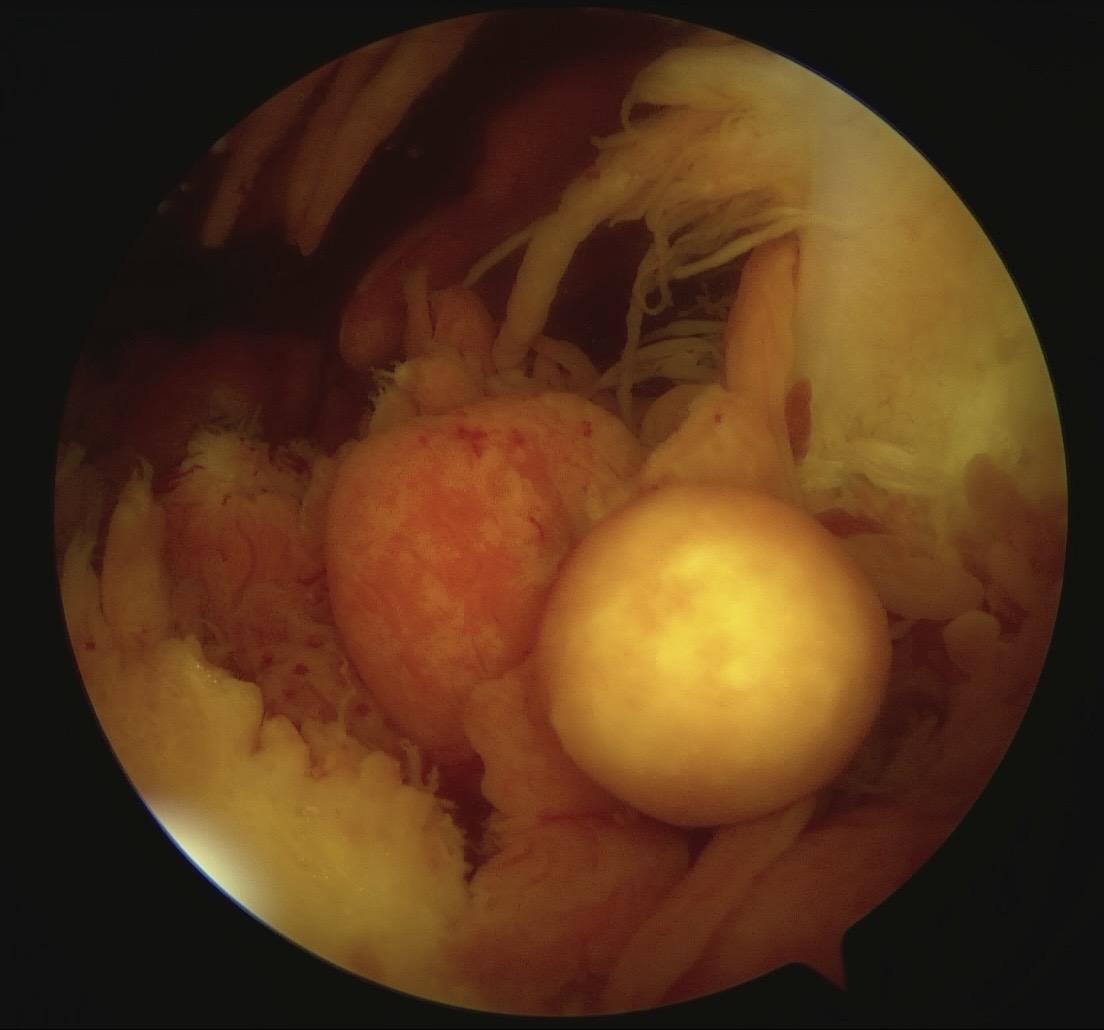

色素沉着绒毛结节性滑膜炎。膝关节反复肿,弥漫型色绒,(PVNS)